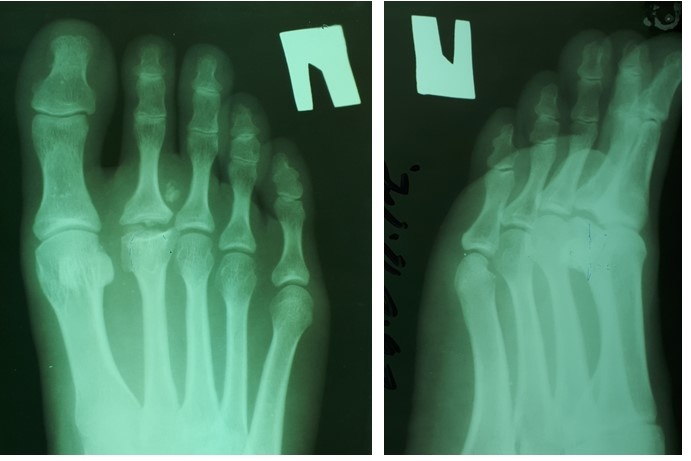

На рентгенограммах визуализируются крупные остеофиты по тыльной поверхности головки и свободные внутрисуставные тела.

-2